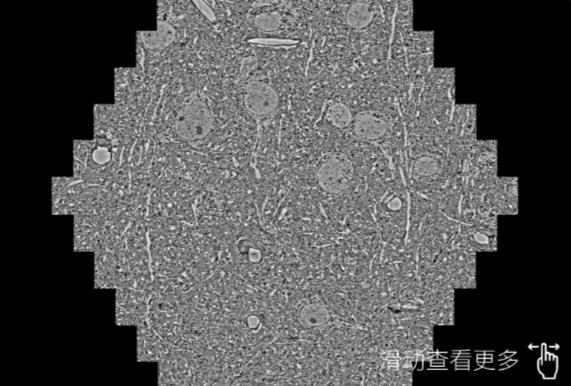

鼠脑切片。左图使用威海蔡司威海扫描电镜MultiSEM706对165μmx143pm面积区域成像,耗时仅需1.5秒。右图为鼠脑切片中30μm区域放大效果。样品由芝加哥大学B.Kasthuri提供。

使用蔡司高速威海扫描电镜MultiSEM对1mm²人脑皮层组织进行高分辨成像,并对其中的各种细胞结构进行三维重构分析。左图展示了2x3mm²组织平面中锥体神经元的三维重构效果。右图显示了局部体积神经元三维重构。图像由哈佛大学chtman实验室提供,渲染图由D. Berger 制作。